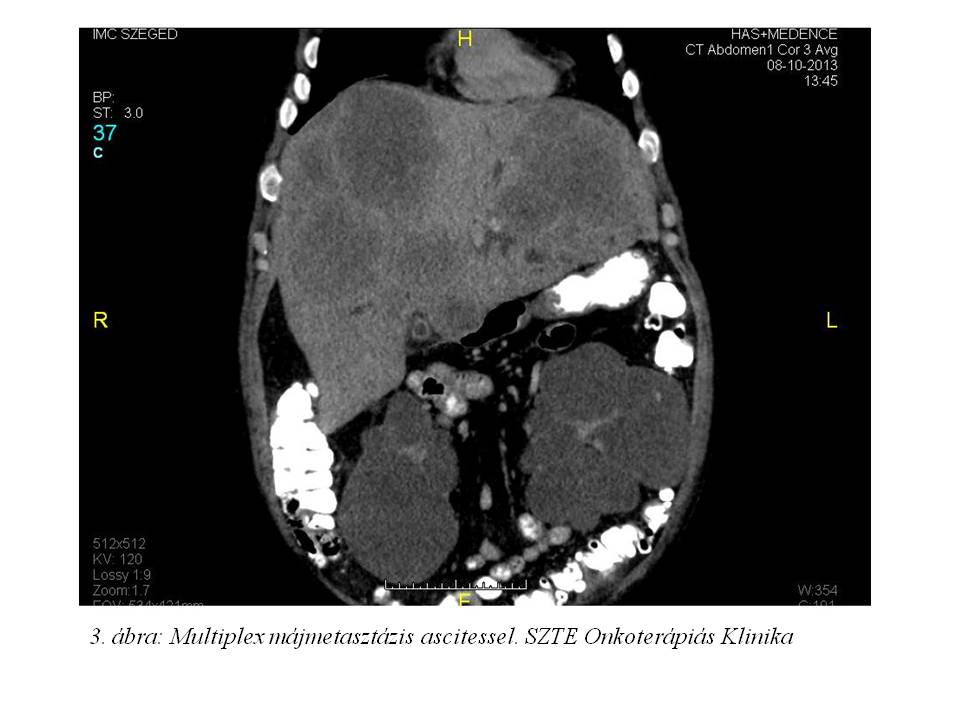

2013 októberében vérszékelés, hasi fájdalom, kb. 10 kg-os fogyás (10%-ot meghaladó súlyvesztés), emelkedő májfunkciós értékek (GOT: 65 U/l, GPT: 67 U/l, GGT: 631 U/l, ALP: 580 U/l, sebi: 34.5 umol/l, dibi: 25.5 umol/l) miatt indult kivizsgálása. Has-kismedence CT (2013.10.08., 1. ábra, 2. ábra, 3. ábra) készült, mely leírta a rectum-sigma átmenet lumenbe domborodó tumorát, multiplex máj metastasist, ascitest. Mellékleletként felvetette a jobb tüdő bázison lévő metasztázis gyanúját. Colonoscopia (2013.10.11.) során a sigmában, az anusgyűrűtől 25 cm-re egy vastag nyélen lévő 6-7 cm-es polyp volt látható. Mivel nem tűnt invazív tumornak, az SZTE Sebészeti Klinikán polypectomiát végeztek. A szövettan azonban malignusan transformálódott tubulovillosus adenomát igazolt adenocarcinomával (pT1). A T1-es kategóriájú daganat multiplex áttétképzését a beteg immunszuprimáltsága magyarázza.